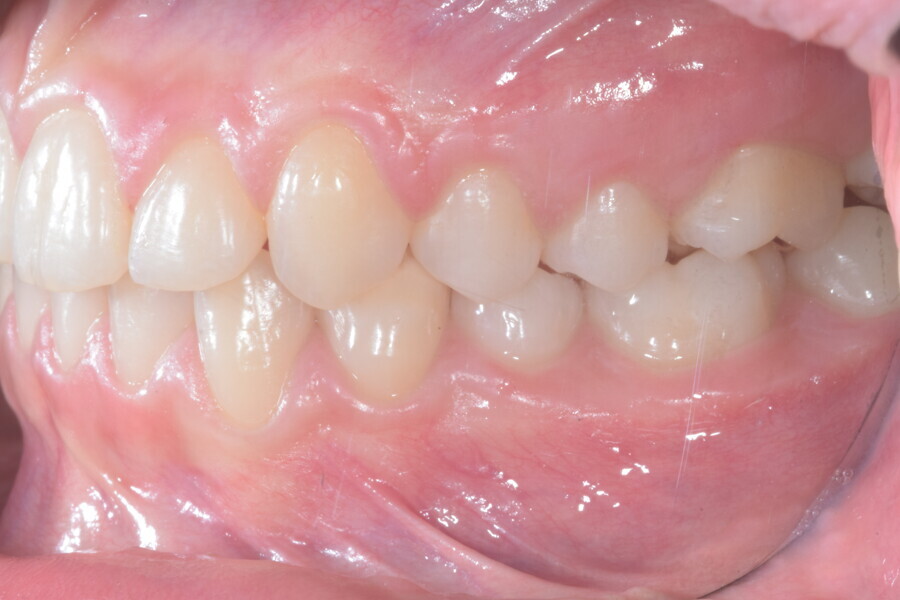

The overall treatment time was 16 months, 11 months of aligner treatment (five months initially for space creation and six months for finalisation after canine eruption) and five months of treatment with MTAs and sectional archwire. At the end of the treatment, a full Class I canine and molar relationship had been obtained, and the impacted canine had fully erupted (Figs. 34–38). A balanced smile with centered midlines had been achieved with an acceptable relationship between the maxillary incisors and lower lip, and torque control of the lateral and posterior segments had generated a broader smile. The limited movement of the upper lip on smiling detected at the beginning was stable, but the smile had improved in terms of expansion and the buccal corridor (Figs. 39–42).